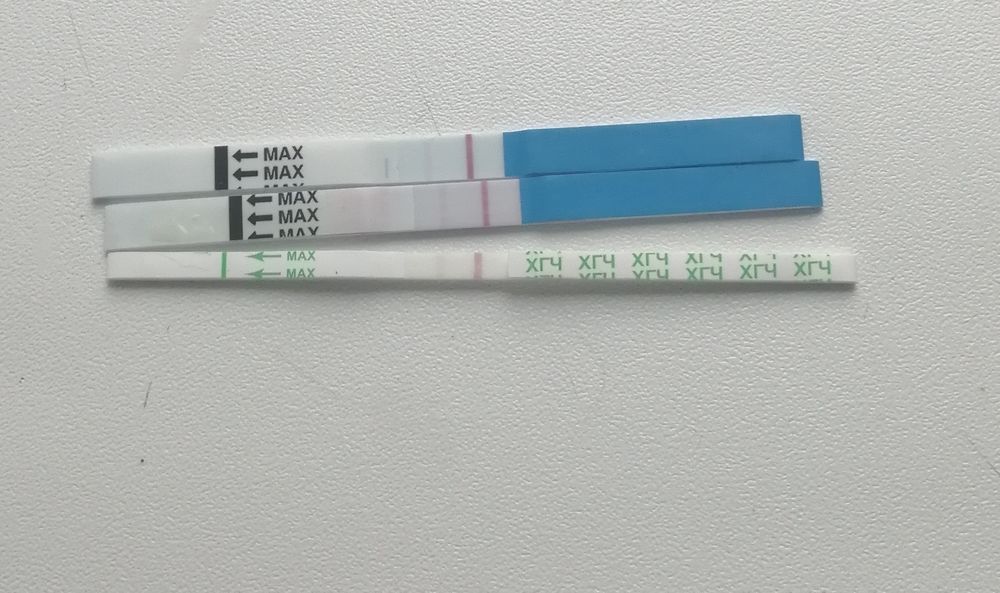

Девочки , плохая очень тема, но хочется успокоится и получить от вас информацию. Может ли замершая беременнось, выкидыш пройти незаметно. Без болей, кровотечения... Было последнее узи на 6й недели. Два деформированных плодных яйца(не знаю почему деформированные). Далось мне сдать тесты три разные, фото прикрепила. Последний хгч был 29октября 152000.